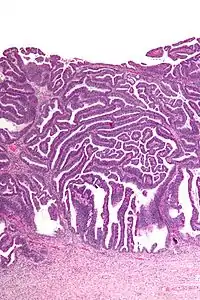

| Micrograph of a villoglandular adenocarcinoma the cervix. H&E stain. | |

The name of the lesion describes it microscopic appearance. It has nipple-like structures with fibrovascular cores (papillae) that are long in relation to their width (villus-like), which are covered with a glandular pseudostratified columnar epithelium.